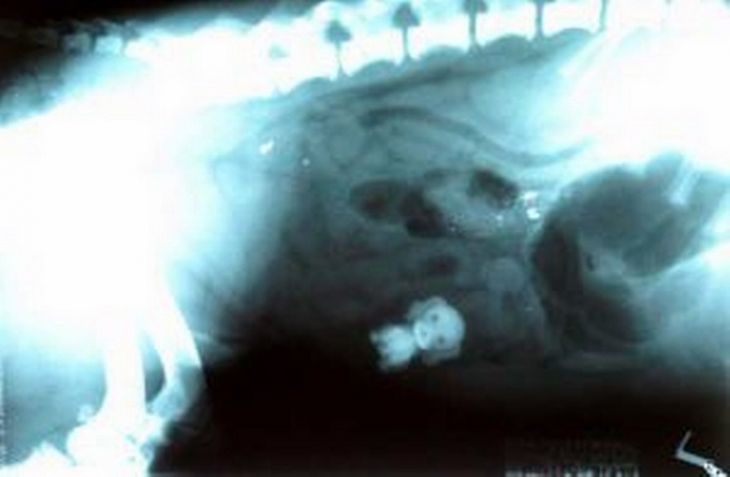

Hračkársky psík

Alfie nezniesol v dome žiadnu konkurenciu. Preto prehltol hračku psíka, ktorá bola pôvodne súčasťou hračkárskeho domčeka jeho ľudskej sestričky. Po operácií sa Alfie opäť cíti v poriadku.

(Zdroj: Manchester Evening News)